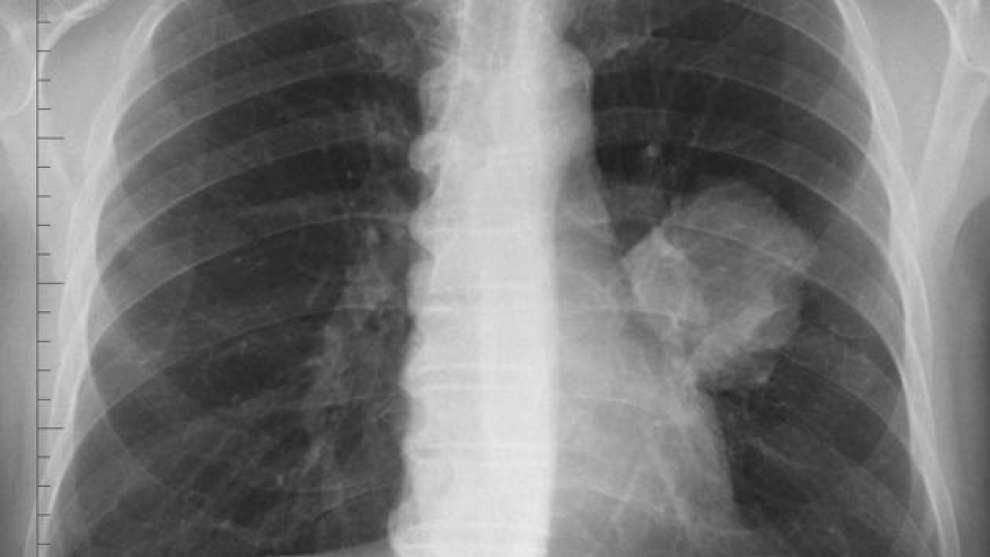

El anticuerpo monoclonal Pembrolizumab es eficaz en el tratamiento de primera línea de pacientes con cáncer de pulmón no microcítico (CPNM) metastásico, según los resultados de dos estudios presentados en el Congreso anual de la Sociedad Europea de Oncología Médica (ESMO). El tratamiento con esta “bala mágica” puede producir una mejora significativa con respecto a la quimioterapia en una amplia gama de pacientes.

En este sentido, estos estudios pueden representar un punto de inflexión en los esfuerzos internacionales para controlar el cáncer de pulmón. En concreto, en el estudio ‘Keynote-024’, cuyos datos han sido publicados en The New England Journal of Medicine y en el que se evaluó a pacientes con CPNM escamoso y no escamoso cuyos tumores expresaban niveles elevados de PD-L1, este fármaco de MSD produjo una reducción del 50 por ciento del riesgo de progresión de la enfermedad o de muerte y una reducción del 40 por ciento del riesgo de muerte en comparación con el doblete de quimioterapia con platino, el tratamiento de referencia actual.

Se trata del único tratamiento anti-PD-1 que hasta la fecha ha conseguido demostrar una supervivencia libre de progresión (SLP) y una supervivencia global (SG) mejores que la quimioterapia como tratamiento de primera línea del CPNM escamoso y no escamoso en pacientes con tumores que expresan niveles elevados de PD-L1 y que no tienen alteraciones genéticas en el EGFR o en el ALK.

Asimismo, en la cohorte ‘G’ del estudio ‘Keynote-021’, publicada en ‘The Lancet Oncology’ y formada por pacientes con CPNM no escamoso metastásico con diferentes niveles de expresión de PD-L1, ‘Keytruda’ más quimioterapia (carboplatino más pemetrexed) alcanzó una tasa de respuesta objetiva (TRO) del 55 por ciento, frente a una TRO del 29 por ciento con la quimioterapia sola (el tratamiento de referencia), y redujo el riesgo de progresión de la enfermedad o de muerte en un 47 por ciento.